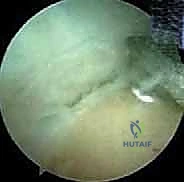

3. الاستكشاف التشخيصي بالمنظار:

يتم إدخال كاميرا المنظار عالية الدقة. يقوم الدكتور هطيف بإجراء فحص شامل وفحص ديناميكي للمفصل من الداخل، لتقييم حالة الغضاريف، البحث عن الأجسام الحرة (Loose bodies) الناتجة عن تفتت العظام، وتقييم حجم النتوءات العظمية في الناتئ المرفقي.

4. إزالة النتوءات العظمية (Osteophyte Excision):

هذه هي الخطوة الأكثر دقة وحساسية، وهنا تتجلى خبرة الأستاذ الدكتور محمد هطيف. باستخدام أدوات دقيقة (Burr)، يقوم بنحت وإزالة النتوءات العظمية الخلفية التي تسبب الانحشار.

5. تنظيف المفصل والإغلاق:

بعد التأكد من إزالة كافة العوائق العظمية واستعادة مدى الحركة الكامل (Extension) أثناء وجود المريض تحت التخدير، يتم غسل المفصل جيداً بسائل معقم لإزالة أي بقايا دقيقة. تُغلق الشقوق الصغيرة بغرزة واحدة لكل شق، وتُوضع ضمادة ضاغطة خفيفة.